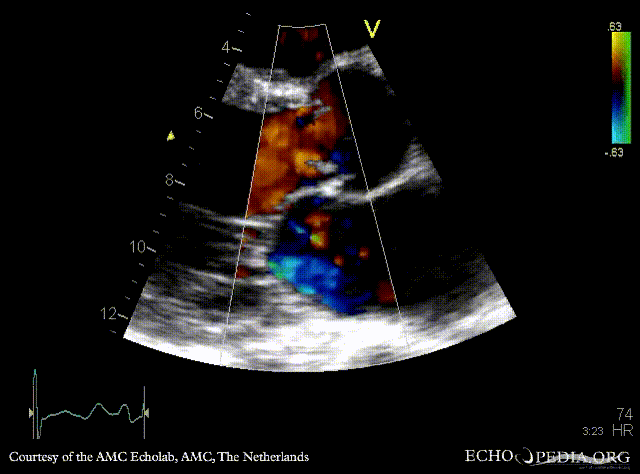

M-Mode through aortic valve PLAX: Color Doppler signal shows severe aortic regurgitation